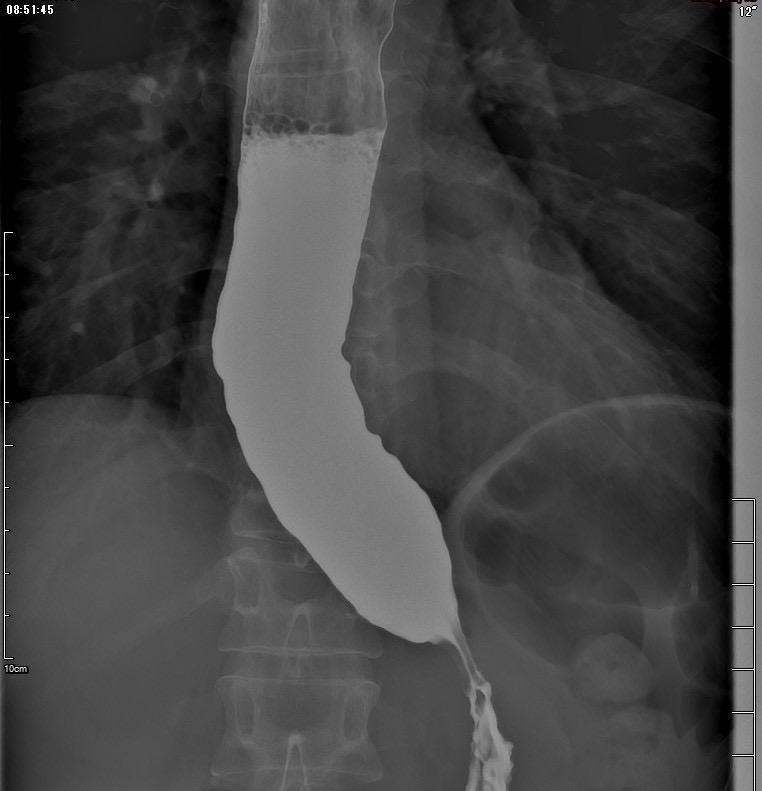

果不其然,食道攝影顯示,患者食道呈現典型的鳥嘴狀(如下圖),檢查食道壓力的過程中,下食道括約肌也沒辦法適當放鬆,食道蠕動收縮不正常,喝下去的水都滯留在食道無法順利流進胃部,因此診斷為「食道弛緩不能」。經討論,將她轉至醫學中心接受內視鏡手術後,終於可以正常進食。

▲患者食道攝影畫面。(圖片/葉秉威提供)